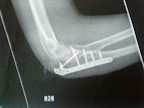

I broke my olecranon in July 09 crashing. Blew the ball off and fractured the bone in a couple of places. Also fractured a rib, which led to a collapsed lung.

I had a plate and five screw put in the day after. Then 4 weeks in plaster, followed by three months or more of physio to get movement back.

I could only bend my arm about 30 degrees at first! But now I can fully bend my arm but am probably 5 degrees off fully straightening it and can't lock the arm out. I also get some arthritic pain now and again, excruciating pain if I knock it.

[img] "[/img]

I've been back on the bike since around March, on and off road. No real problems, it's just weak and I can't lean on the metalwork. The skin is also very sensitive.

Just got back from the hospital and the metalwork is being taken out in October. Its not completely necessary, but is a good idea in case I break it again. I'll be off the bike for a month whilst the bone fills the holes.